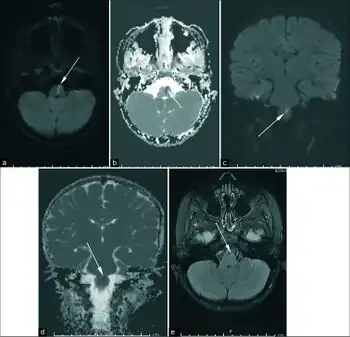

Weber's syndrome is the only form of alternating hemiplegia that is somewhat easy to diagnose beyond the general criteria. Although Weber's syndrome is rare, a child born with the disorder typically has a port-wine stain on the face around the eye. While the port-wine stain does not necessarily mean the child has Weber's syndrome, if the port-wine stain involves the ophthalmic division of the trigeminal nerve than the likelihood of it being weber's syndrome greatly increases. If a port-wine stain around the eye is found, the patient should be screened for intracranial leptomeningeal angiomatosis. Magnetic resonance imaging (MRI) can be used to determine the presence and severity while computed cranial tomography can be used to determine the effect. MRI is the preferred diagnostic test on children presenting with port-wine stain. Other imaging techniques can be used in addition to further determine the severity of the disorder. The initial diagnosis is made based on the presence of neurologic and ophthalmic disease but the disease progresses differently in each patient so after initial diagnosis the patient should be monitored frequently in order to handle further complications resulting from the syndrome.[7]